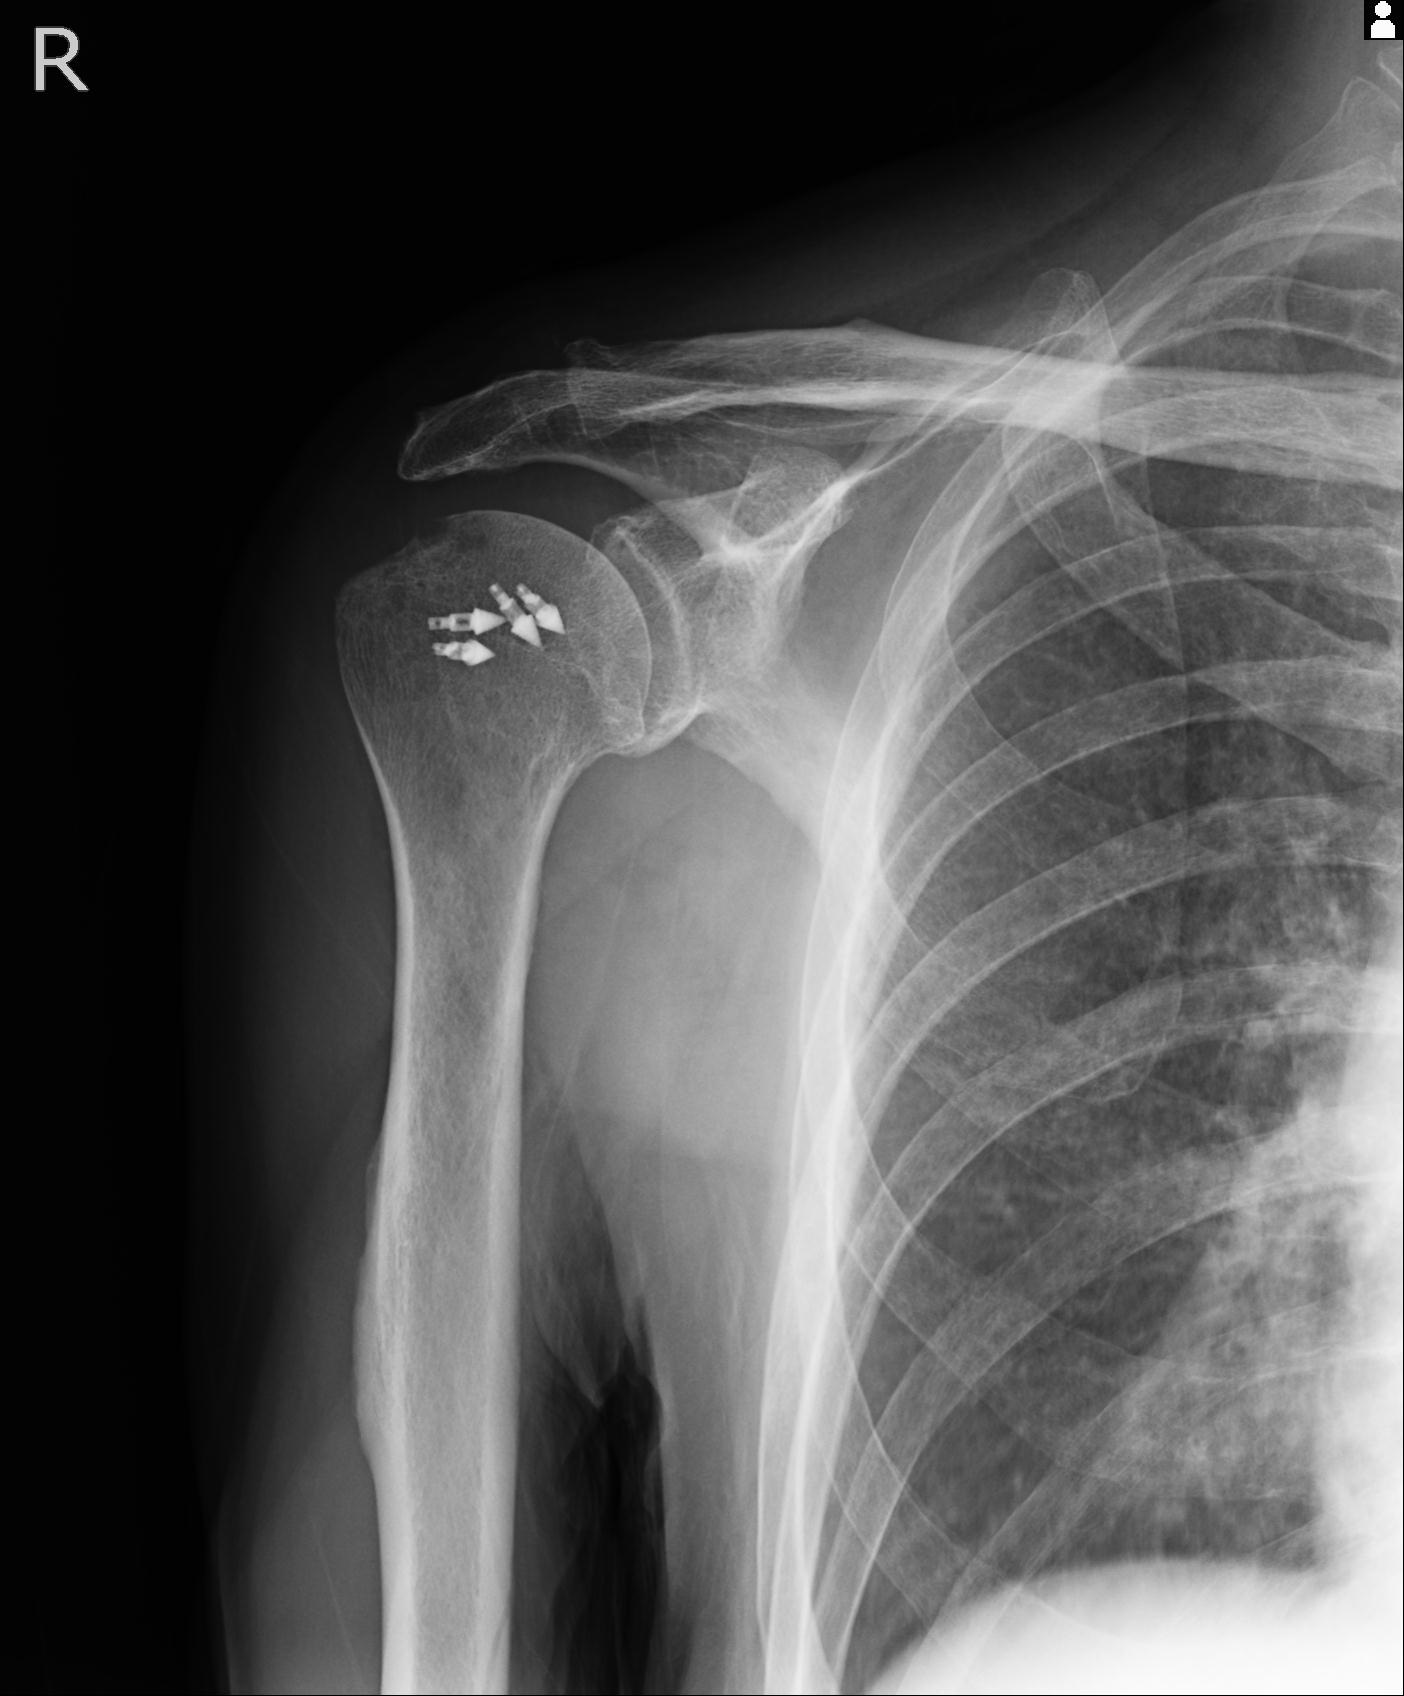

60058 3/9 11/4 右肩 2R+MRI 73歳男性 肩腱板損傷